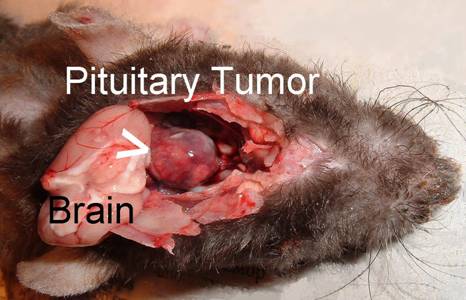

This picture shows the inside of the skull with the brain

removed. This

photo shows the brain pulled back revealing a very large and

The small pituitary gland can be seen between the 2 ridges. obvious pituitary tumor.